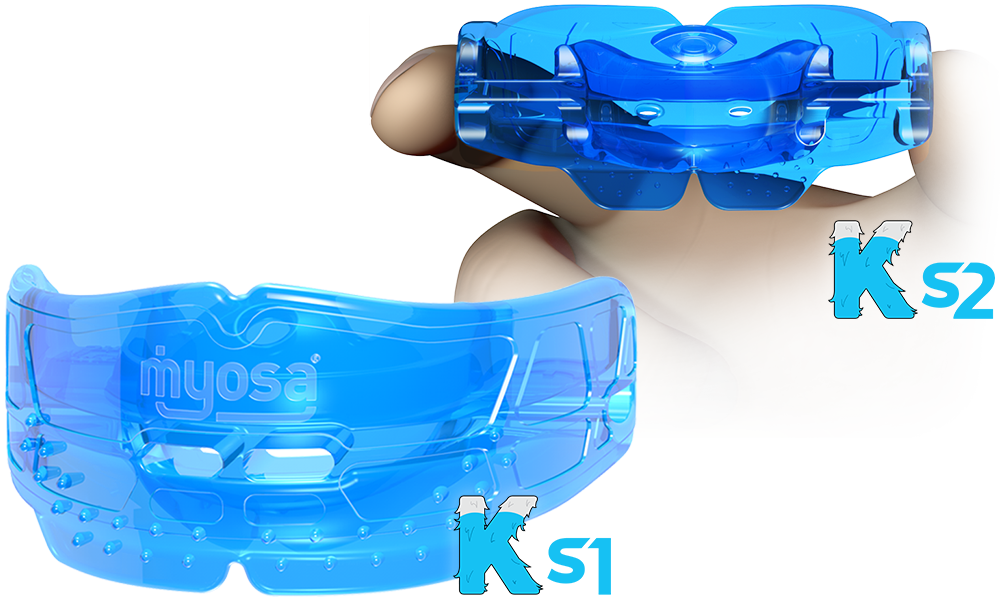

Myofunctional Therapy (MFT): Fixing the Cause

Fixing the Cause, Not Just the Effect

Orthodontics aligns teeth.

Myofunctional therapy (MFT) corrects the orofacial muscle patterns that led to the orthodontic problem in the first place.

MFT focuses on:

- Correct swallow mechanics

- Nasal breathing encouragement

- Tongue posture training

- Lip closure and relaxed oral rest posture

When used in conjunction with orthodontics, MFT supports:

- Greater treatment stability

- Reduced relapse

- Enhanced airway and swallowing function

The analogy is simple: fix the dripping tap before mopping up the floor. No Ordinary Dentistry